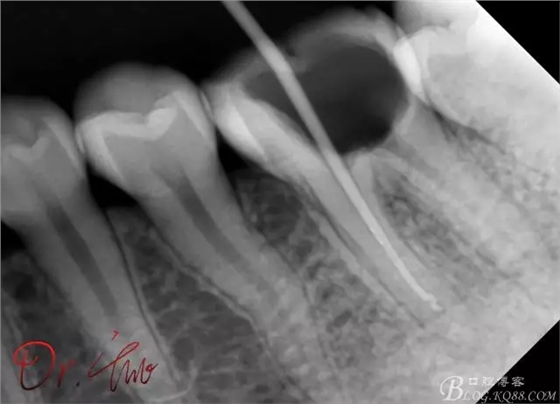

初診照

拍片確定長度